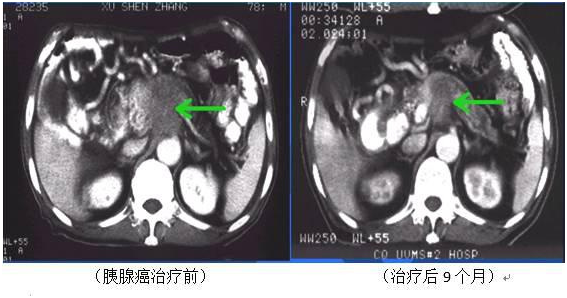

四、射频、微波肿瘤消融治疗

适用范围:

1、肿瘤不能切除

2、肿瘤直径小于7厘米

3、少于8个病灶

4、病灶总体体积小于肝脏总体积的20%

5、任何肝外病灶局限于结节(6个或更少,3CM或更小)